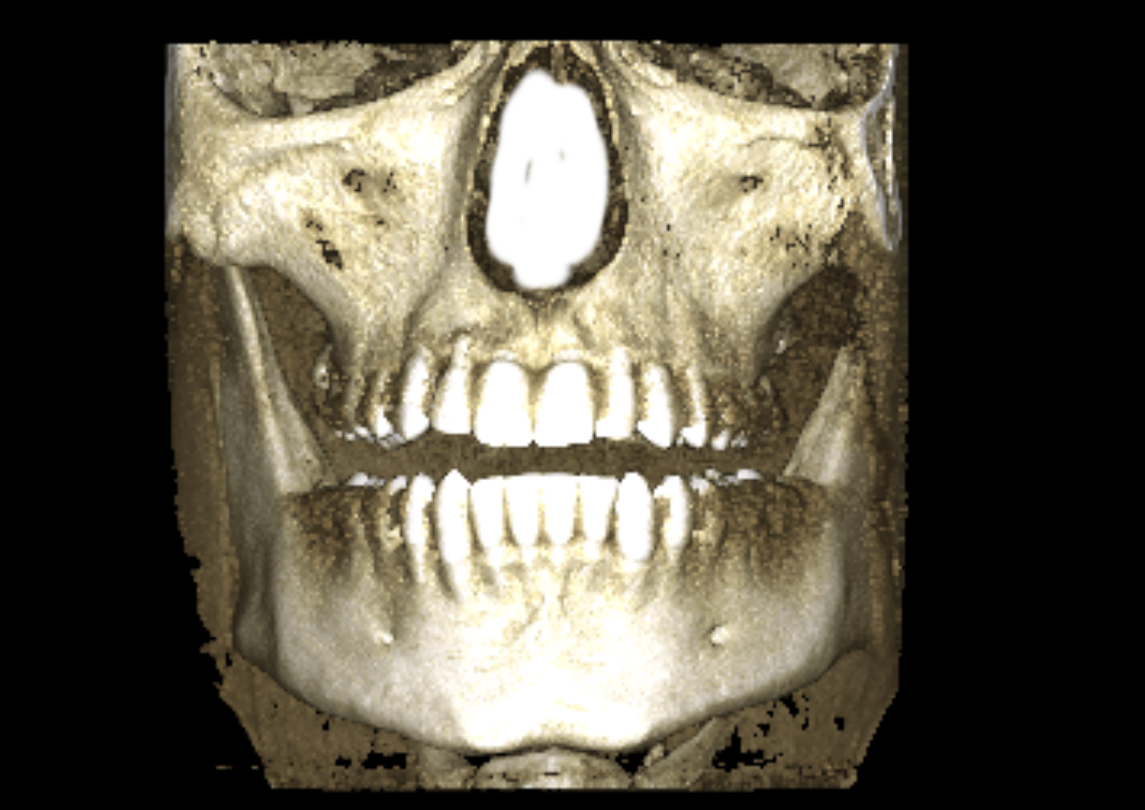

seems to be centered, it's just the alveolar bone playing tricks with you head, your teeth are a lil overcrowded and the "midline" in the teeth has "shifted" (thankfully because of the xray you can see that with braces a clear aligner or even a toothborne expander you could fix your overcrowded lower teeth and move the "mid-line" to the right spot, your occlusion doesn't follow the "guide lines" of the bones also I notice that the upper jaw seems to be inlign with the "midline"(teeth and the base of the nasal cavity as you can see in the image)

The alveolar bone in the upper jaw seems to be shifted